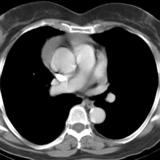

Part'l absc peric CT

Date: 07/23/2006

Views: 3171